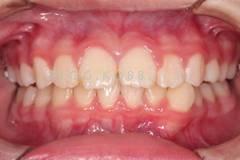

下面這個(gè)小患者就存在需早期矯正的問題。通過早期矯正,在不長(zhǎng)的時(shí)間內(nèi)就達(dá)到極為明顯的療效。她的情況如果等到牙齒替換完畢后再解決,矯治的難度則會(huì)非常大。

早期矯正中